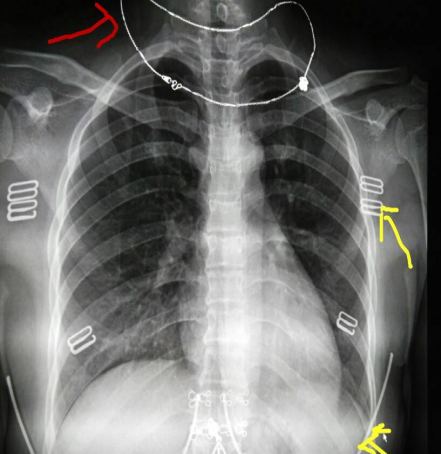

对比图如下:

x光材质怎么调【科普加油站】放射检查穿对衣服,让健康“一目了然”_https://www.jmylbn.com_新闻资讯_第5张

常规胸片(胸部X光片)

含有项链、内衣扣及钢圈遮物的胸片

因项链、文胸(钢圈、排扣)、束腰带产生了明显的白色亮影,类似的还有磁疗内裤(材质内含金属),在图像上呈现出一颗颗白色亮点,图像会干扰医生观察。